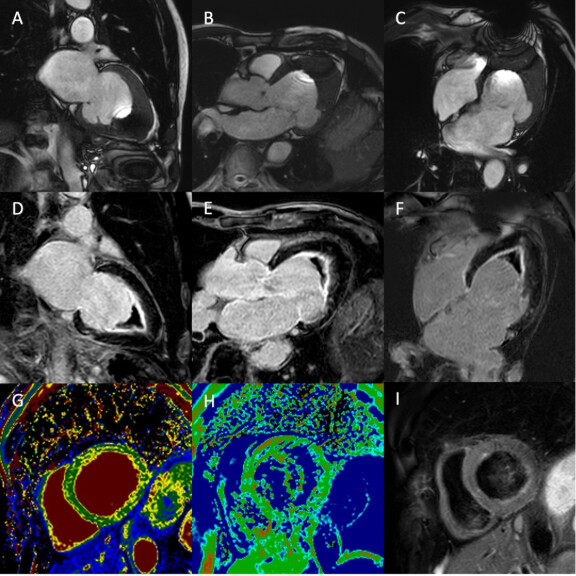

Kardio-MRT-1zu1-576x576

Abb.: Patient mit einer phänotypischen Endomyokardfibrose. Der linksventrikuläre Apex ist deutlich verplumpt (Cine-Aufnahmen, A-C). C zeigt ein typisches Artefakt durch einen Metallfremdkörper im Bereich der Thoraxwand auf Höhe des Zwerchfells. In den Spätaufnahmen (D-F) ist ein ausgeprägtes endokardiales Late Gadolinium Enhancement apikal und mittventrikulär nachweisbar sowie thrombotische Auflagerungen in diesem Bereich. Die basale Aufnahme der T1-Map (G) ist unauffällig, in der T2-Map basal (H) und T2-Blackbloodaufnahme basal (I) ist kein myokardiales Ödem nachweisbar.